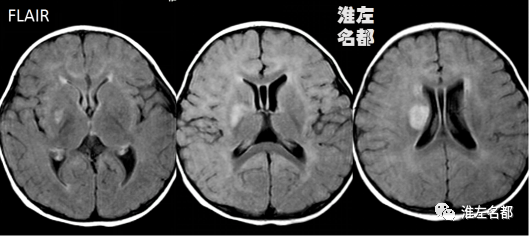

2010-9-13 MRI

△颅脑T2WI和FLAIR:右侧基底节区梗死高信号。